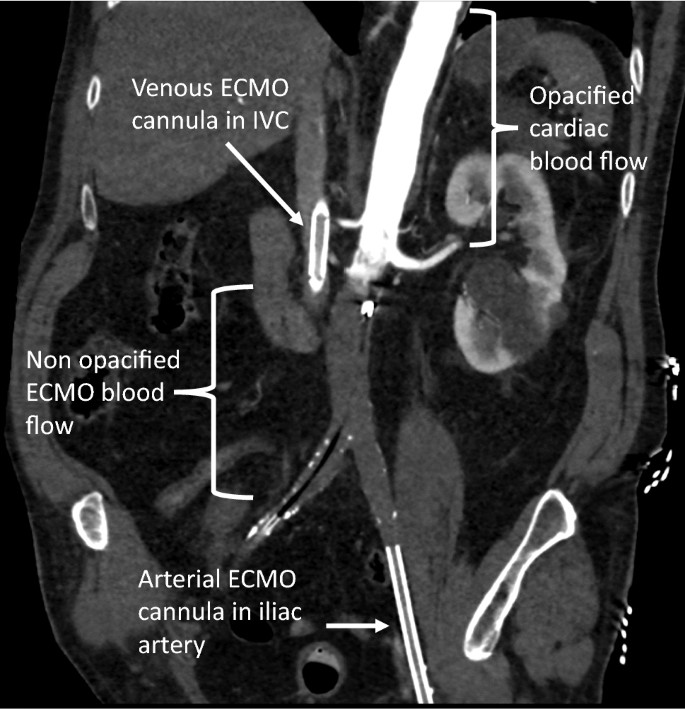

Zongwei Gao Finally Have A Chance To Observe The Retrograde Blood Flow Inside The Aorta On Ecmo In The Catheter Room